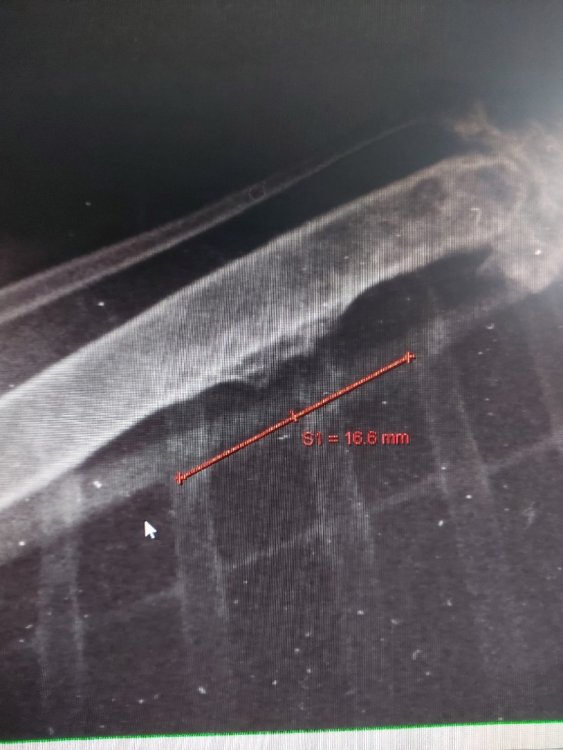

День добрый. Серая ворона, возраст 1 год. На последнем ренгене заметила на одной из костей левого крыла вот такой нарост. Что бы это могло быть? Врач высказала мнение, что возможно результат травмы. У вороны переломы правого крыла (внутрисуставной лопаточно-ключичный и перелом ключицы) из-за этого не всегда успешно приземляется когда прыгает и иногда падает.